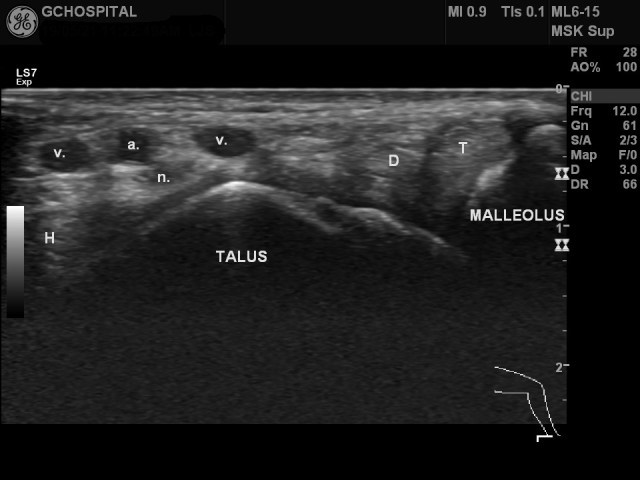

T : tibialis posterior tendon

D : flexor digitorum longus tendon

H : flexor hallucis longus

a. : posterior tibial artery

v. : posterior tibial veins

n. : posterior tibial nerv

내측 복사뼈보다 위쪽에서 얻은 발목 내측(posteromedial compartment)의 초음파영상입니다. flexor hallucis longus muscle과 tenon의 일부가 함께 보입니다. 통상 교과서를 보면, posterior tibial artery보다 posterior tibial nerve가 더 뒤쪽에 위치하는것처럼 기술되 있는 경우가 많은데, 실제로 보면 위의 영상처럼 뒷쪽이라기 보다는 더 깊은 곳에 위치해있는 경우가 더 흔한것 같습니다.

여기서 tibialis posterior nerve주변에 신경과 혈관을 압박하고 있는 구조물이 있는지를 확인하는 것이 발목쪽의 구획증후군(compartment syndrome)을 진단하는데 매우 중요합니다. 언급하고 있는 구조물들을 둘러싸고 있는 얇은 막이 flexor retinaculum입니다.